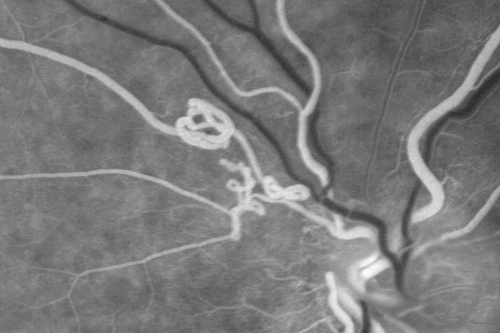

Anomalous Branch Retinal Artery

59-year-old man OD 20/25, OS 20/25. TORTUOUS RETINAL ARTERY – LEF EYE

(POSSIBLE GROUP 2 WYBURN-MASON SYNDROME

POSSIBLE ACEPHALIC MIGRAINES )